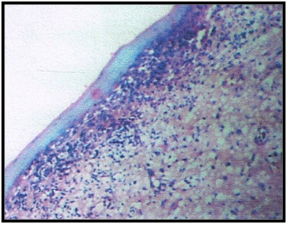

2. Incisional biopsy (Figure 4)

Figure 4The Photomicrograph of the lesion.

The histopathological examination of the tissue biopsied revealed it to be case of lichen planus. The hematoxylin and eosin stained section showed epithelium and connective tissue. The epithelium was parakeratinized stratified squamous and hyperplastic in few areas. Few areas also showed atrophic epithelium. Underlying connective tissue showed a dense band of chronic inflammatory cells predominantly lymphocytes along with plasma cells. Prominent blood vessels were seen in the section. Saw tooth rete pegs, which are the hallmarks of lichen planus were clearly evident in the photomicrographs .